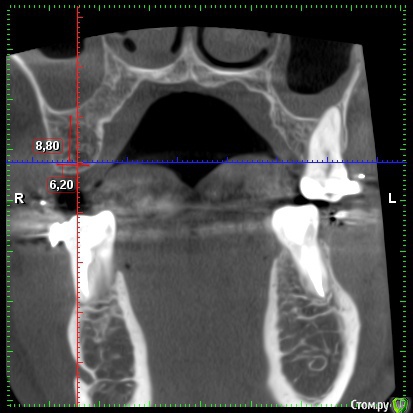

red_butler Опубликовано 1 декабря, 2019 Поделиться Опубликовано 1 декабря, 2019 Это нормальная практика? да Хватает ли костной ткани в области данных зубов? по высоте хватает, ширину нужно смотреть на Кт (качать весь архив не буду) покажите срезы областей интереса Будет ли влиять выбор производителя/модели имплантата на необходимость наращивания костной ткани? как правило не влияет 1 Ссылка на комментарий

red_butler Опубликовано 1 декабря, 2019 Поделиться Опубликовано 1 декабря, 2019 костная пластика не нужна, разве что небольшой закрытый синуслифтинг слева Ссылка на комментарий

Irouil Опубликовано 3 декабря, 2019 Поделиться Опубликовано 3 декабря, 2019 Что касается синус-лифтинга, то по 26-му зубу мне сообщили, что он действительно не нужен, а вот по 16-му что-то вроде пограничного положения. Все наоборот. Но синус лифт там требуется минимальный. Астра тёк прекрасные имплантаты Ссылка на комментарий